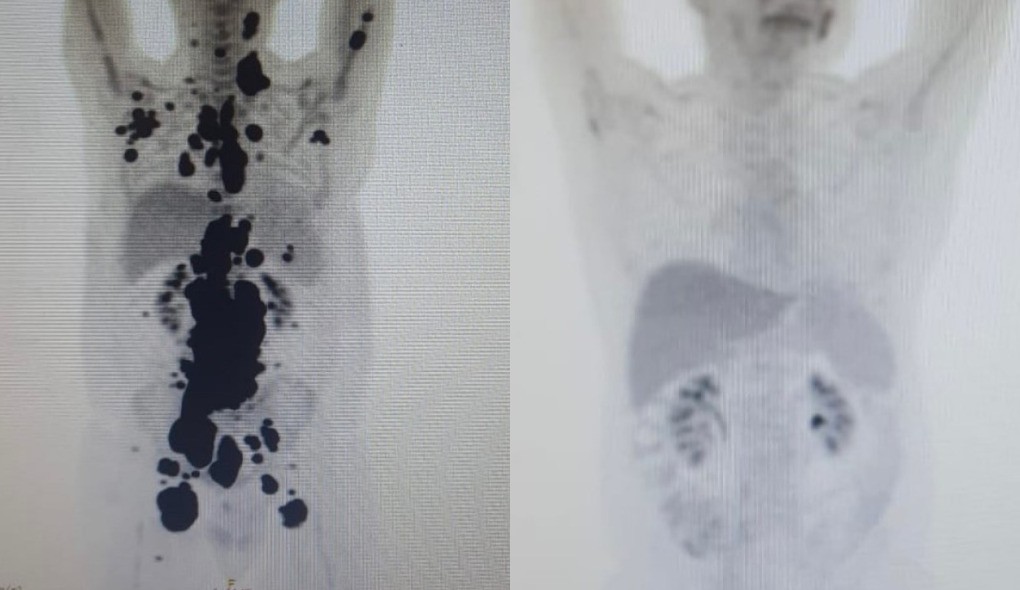

Terapia celular no SUS promove remissão completa de câncer em paciente após 13 anos de luta

Paciente com linfoma tem resposta rápida e sem tumores após tratamento experimental com CAR-T Cell no sistema público de saúde.